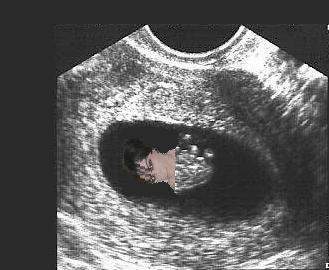

We had a little scare on Friday and I was given an early ultrasound. Fortunately, everything looked good. Baby measured just right for it's age (about 8wks) at 1.5cm and the little heart was beating along at a steady 145bpm (also very good). Everything else looked good as well. I thought I would include a picture for anyone interested.

baby2.jpg

baby2.jpg [ 19.12 KiB | Viewed 4719 times ]